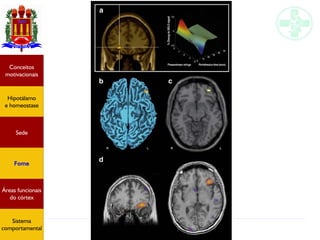

Palatabilidade (valor hedônico)

Berridge & Kringelbach, 2008